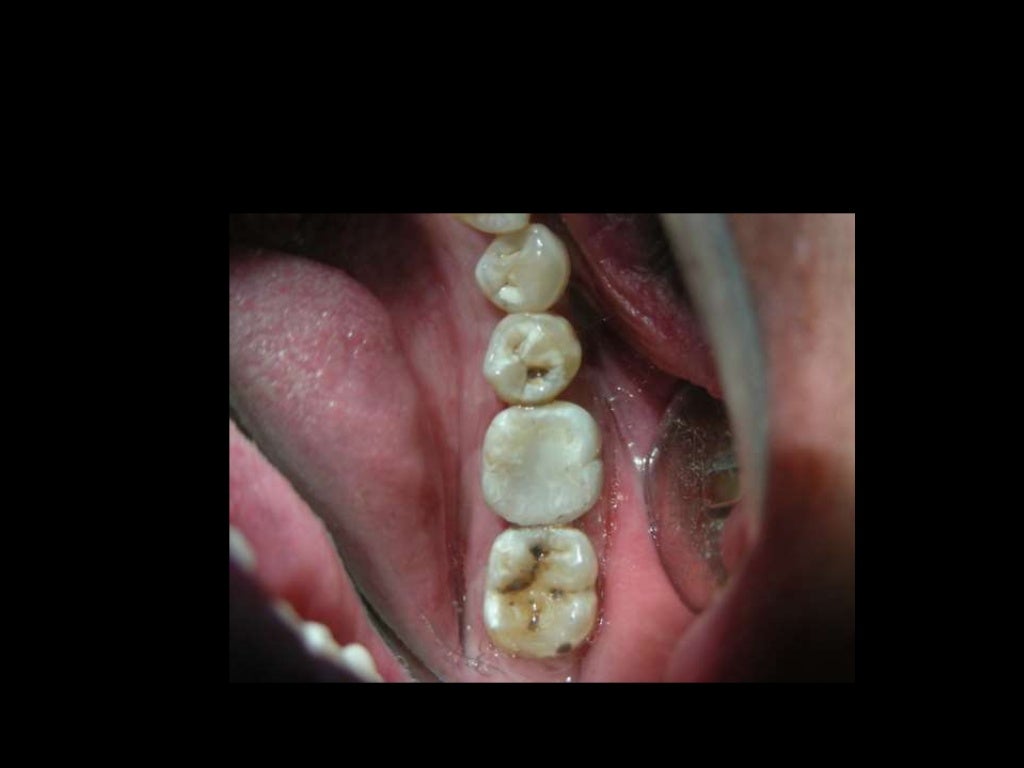

What Are Posterior Composites . In its most recent formulations (microhybrid, nanoparticles, nanohybrid), composite resin has become the most widely used material for restoring posterior teeth because of its biomechanical and esthetic properties. From placing in increments to filling in bulk, learn how to improve placement of posterior composites for lasting restorative success. Compared to amalgam, its use not only improves aesthetics. Understanding these categories can help dentists choose the best materials for posterior placement. Dental composite categories can be. Given today’s overhead per hour, dentist’s need material and technology advancements so that posterior composites can be placed faster,. These restorations require a heightened attention to detail in the selection of devices,. Direct placement resin composite is revolutionizing the restoration of posterior teeth. As there is a wide variation in the teaching and practice of posterior composite techniques worldwide, this paper aims to provide.

In its most recent formulations (microhybrid, nanoparticles, nanohybrid), composite resin has become the most widely used material for restoring posterior teeth because of its biomechanical and esthetic properties. Understanding these categories can help dentists choose the best materials for posterior placement. Given today’s overhead per hour, dentist’s need material and technology advancements so that posterior composites can be placed faster,. These restorations require a heightened attention to detail in the selection of devices,. As there is a wide variation in the teaching and practice of posterior composite techniques worldwide, this paper aims to provide. Direct placement resin composite is revolutionizing the restoration of posterior teeth. Compared to amalgam, its use not only improves aesthetics. Dental composite categories can be. From placing in increments to filling in bulk, learn how to improve placement of posterior composites for lasting restorative success.